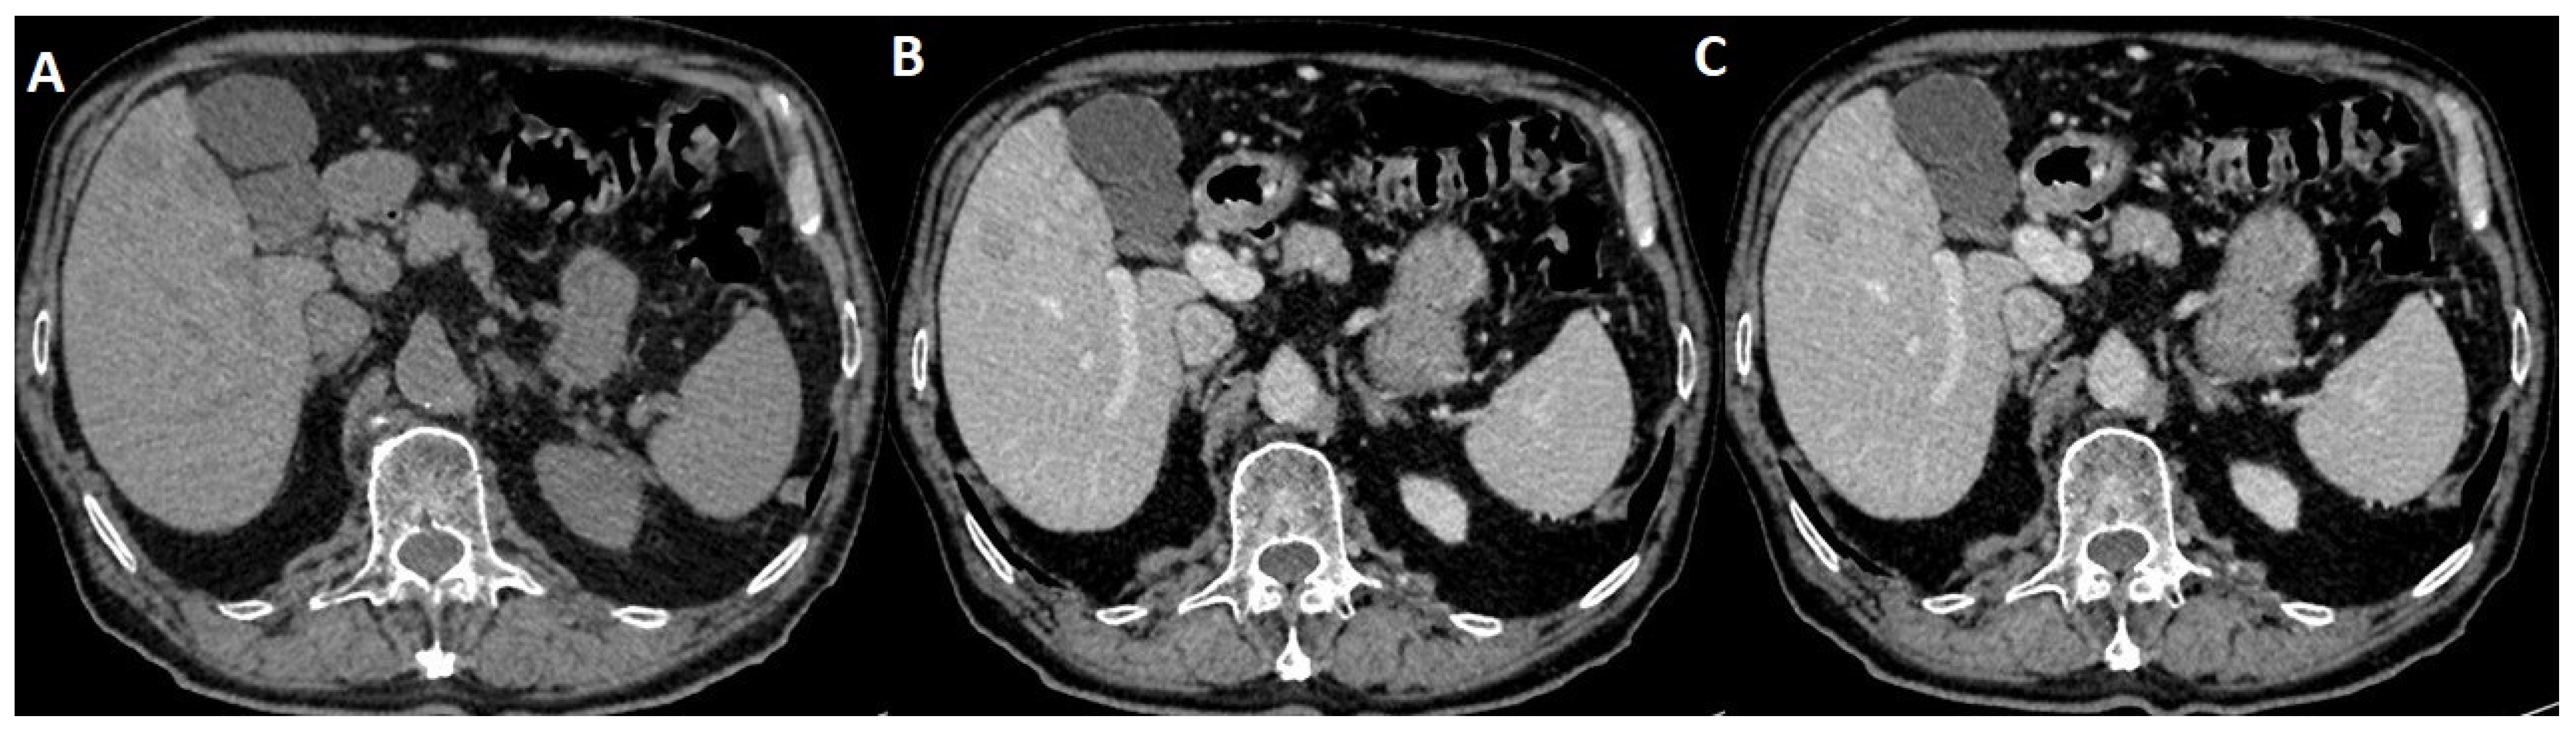

2.3. MRI Dynamic Three-Phasic Scanning